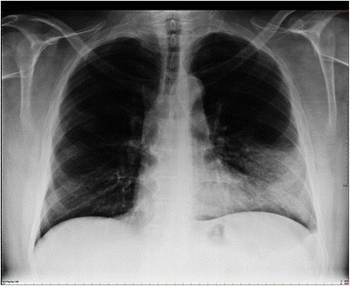

Atypical pneumonia- Chest x-ray, dense infiltration in the left lower lobe

Chest radiographs (X-ray photographs) often show a pulmonary infection before physical signs of atypical pneumonia are observable at all.[5] This is occult pneumonia. In general, occult pneumonia is rather often present in patients with pneumonia and can also be caused by Streptococcus pneumoniae, as the decrease of occult pneumonia after vaccination of children with a pneumococcal vaccine suggests.[16][17]

Infiltration commonly begins in the perihilar region (where the bronchus begins) and spreads in a wedge- or fan-shaped fashion toward the periphery of the lung field. The process most often involves the lower lobe, but may affect any lobe or combination of lobes.[5]